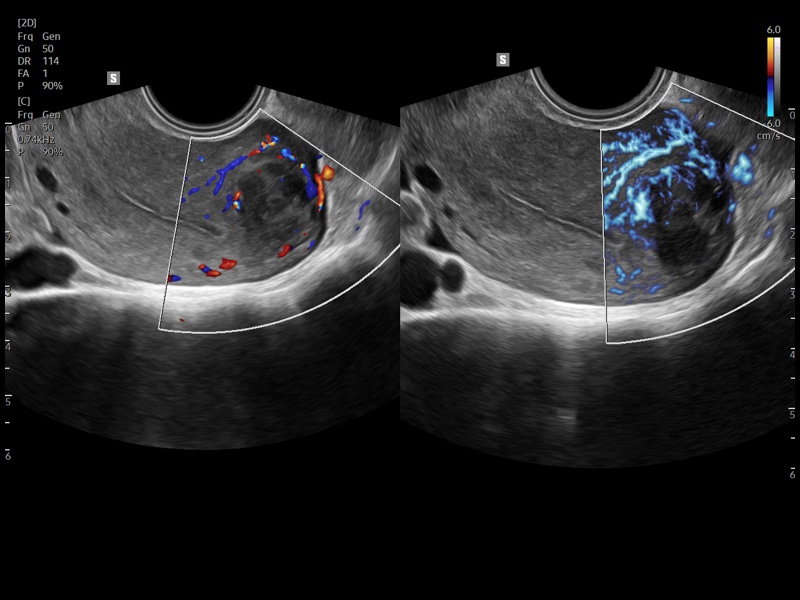

[RU] Ultrasound image №942: Uterine fibroids in CFM (color flow mapping) and MV-Flow™ (microcirculation visualization) mode.

Echogramm was received by ultrasound scanner Z20 (new model).